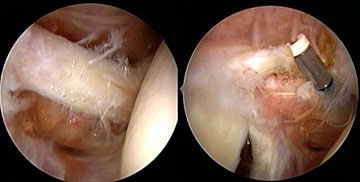

Arthroskopische

Rotatorenmanschettennaht

Die Technik der arthroskopischen RM-Naht hat sich in den letzten

Jahren durch die Einführung von endoskopischen Nahtinstrumenten,

Nahtzangen und Schraubankern deutlich verbessert. Während vor

einigen Jahren meist nur einreihig genäht wurde, ist heute

das Ziel die Ansatzfläche der Sehnen an ihren Anheftungsstellen

(Foot print) großflächig wiederherzustellen. Diesbezüglich

werden heute zweireihige Nähte vorgenommen. Schwierig, aber

technisch machbar ist die arthroskopische Rekonstruktion der Subscapularissehnenausrisse.

Abbildung:

Endoskopische Subscapularissehnenaht |

Endoskopische Supraspinatussehennaht |